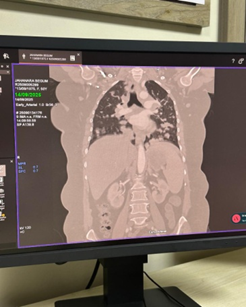

Case Presentation: A 50-year-old female presented with anorexia and cervical lymphadenopathy came for evaluation and management. Chest radiograph and CT scan demonstrated multiple bilateral pulmonary nodules without abdominal organ involvement. Core biopsy of a pulmonary lesion confirmed the diagnosis of NHL, B-cell type.

• Chest radiograph revealed multiple nodular opacities in both lung fields.

• CT chest demonstrated numerous, variable-sized nodules scattered throughout both lungs, with no mediastinal mass, pleural effusion, or consolidation.

• CT abdomen showed normal hepatosplenic and abdominal organ morphology.